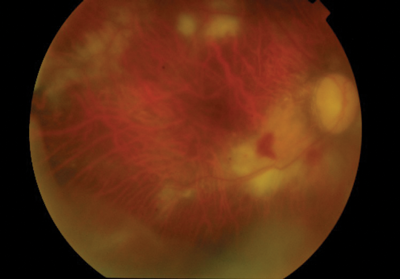

Figure 1: Fundus photograph shows active CMV retinitis four weeks after IVTA in the right eye.

Four weeks following the surgery, the patient presented to eye casualty complaining of misty vision in the right eye with a visual acuity of 6/18 (preoperatively 6/9) and intraocular pressure (IOP) of 16. Keratic precipitates were noted on the endothelium of the cornea of the right eye with 3+ cells in the vitreous. Extensive areas of retinitis around vessels in the mid periphery were noted (Figure 1) and a clinical diagnosis of acute retinal necrosis most likely secondary to herpes simplex virus (HSV) was made. A diagnostic vitreous biopsy was arranged and the patient was started on 2g of valacyclovir three times a day and topical steroids. Polymerase chain reaction (PCR) was negative for HSV and varicella zoster virus (VZV) but positive for cytomegalovirus (CMV). Serologic tests for human immunodeficiency virus (HIV), CMV, toxoplasma and treponema were negative. There were no extraocular signs of CMV infection or pre-existing CMV disease. The valacyclovir was switched to valgancyclovir 900mg twice a day and an intravitreal foscarnet injection (2.4mg) was performed. The retinitis completely resolved within four weeks and visual acuity in the right eye returned to 6/12.